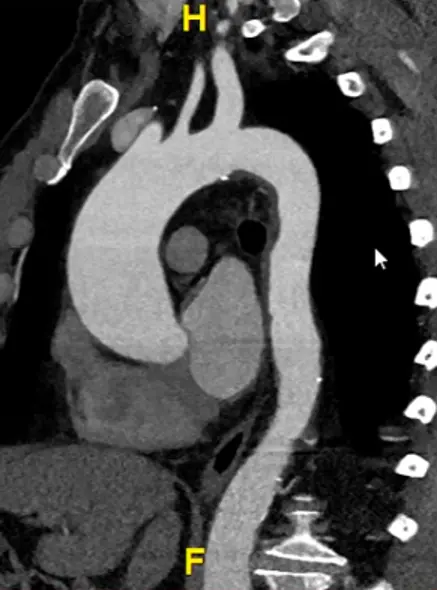

Measure aorta using âcandy caneâ view

- Rotate your cross hairs so you are cutting through both the ascending and descending thoracic aorta.

- Last step is to click the

MPRbutton at the top right and change it toMIP - Hit

Ctrl, hit the button down and drag sideways, you can increase/decrease the slab thickness. For example, this may allow you to capture the entire thickness of the aorta in different planes by manipulating the slab thickness. - Hit

Dto make measurements at different levels of the aorta. Provides a sanity check to make sure you didnât miss a larger/wider part of the aorta. - Right-click and select âCaptureâ to store this image with your measurements.